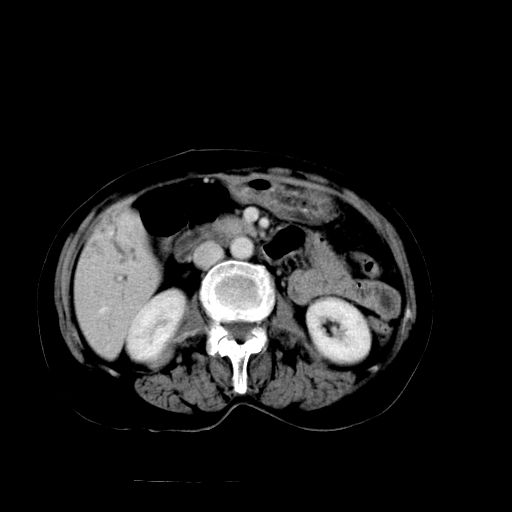

以下是引用卜一在2009-4-7 5:06:00的发言:[br]左右肝内胆管结石伴扩张合并胆系感染;不除外胆管细胞癌可能。支持! [br] [br]

以下是引用随光逐影在2009-4-7 8:21:00的发言:[br]肝内外胆管多发性结石并肝内外胆管扩张;胆系感染。